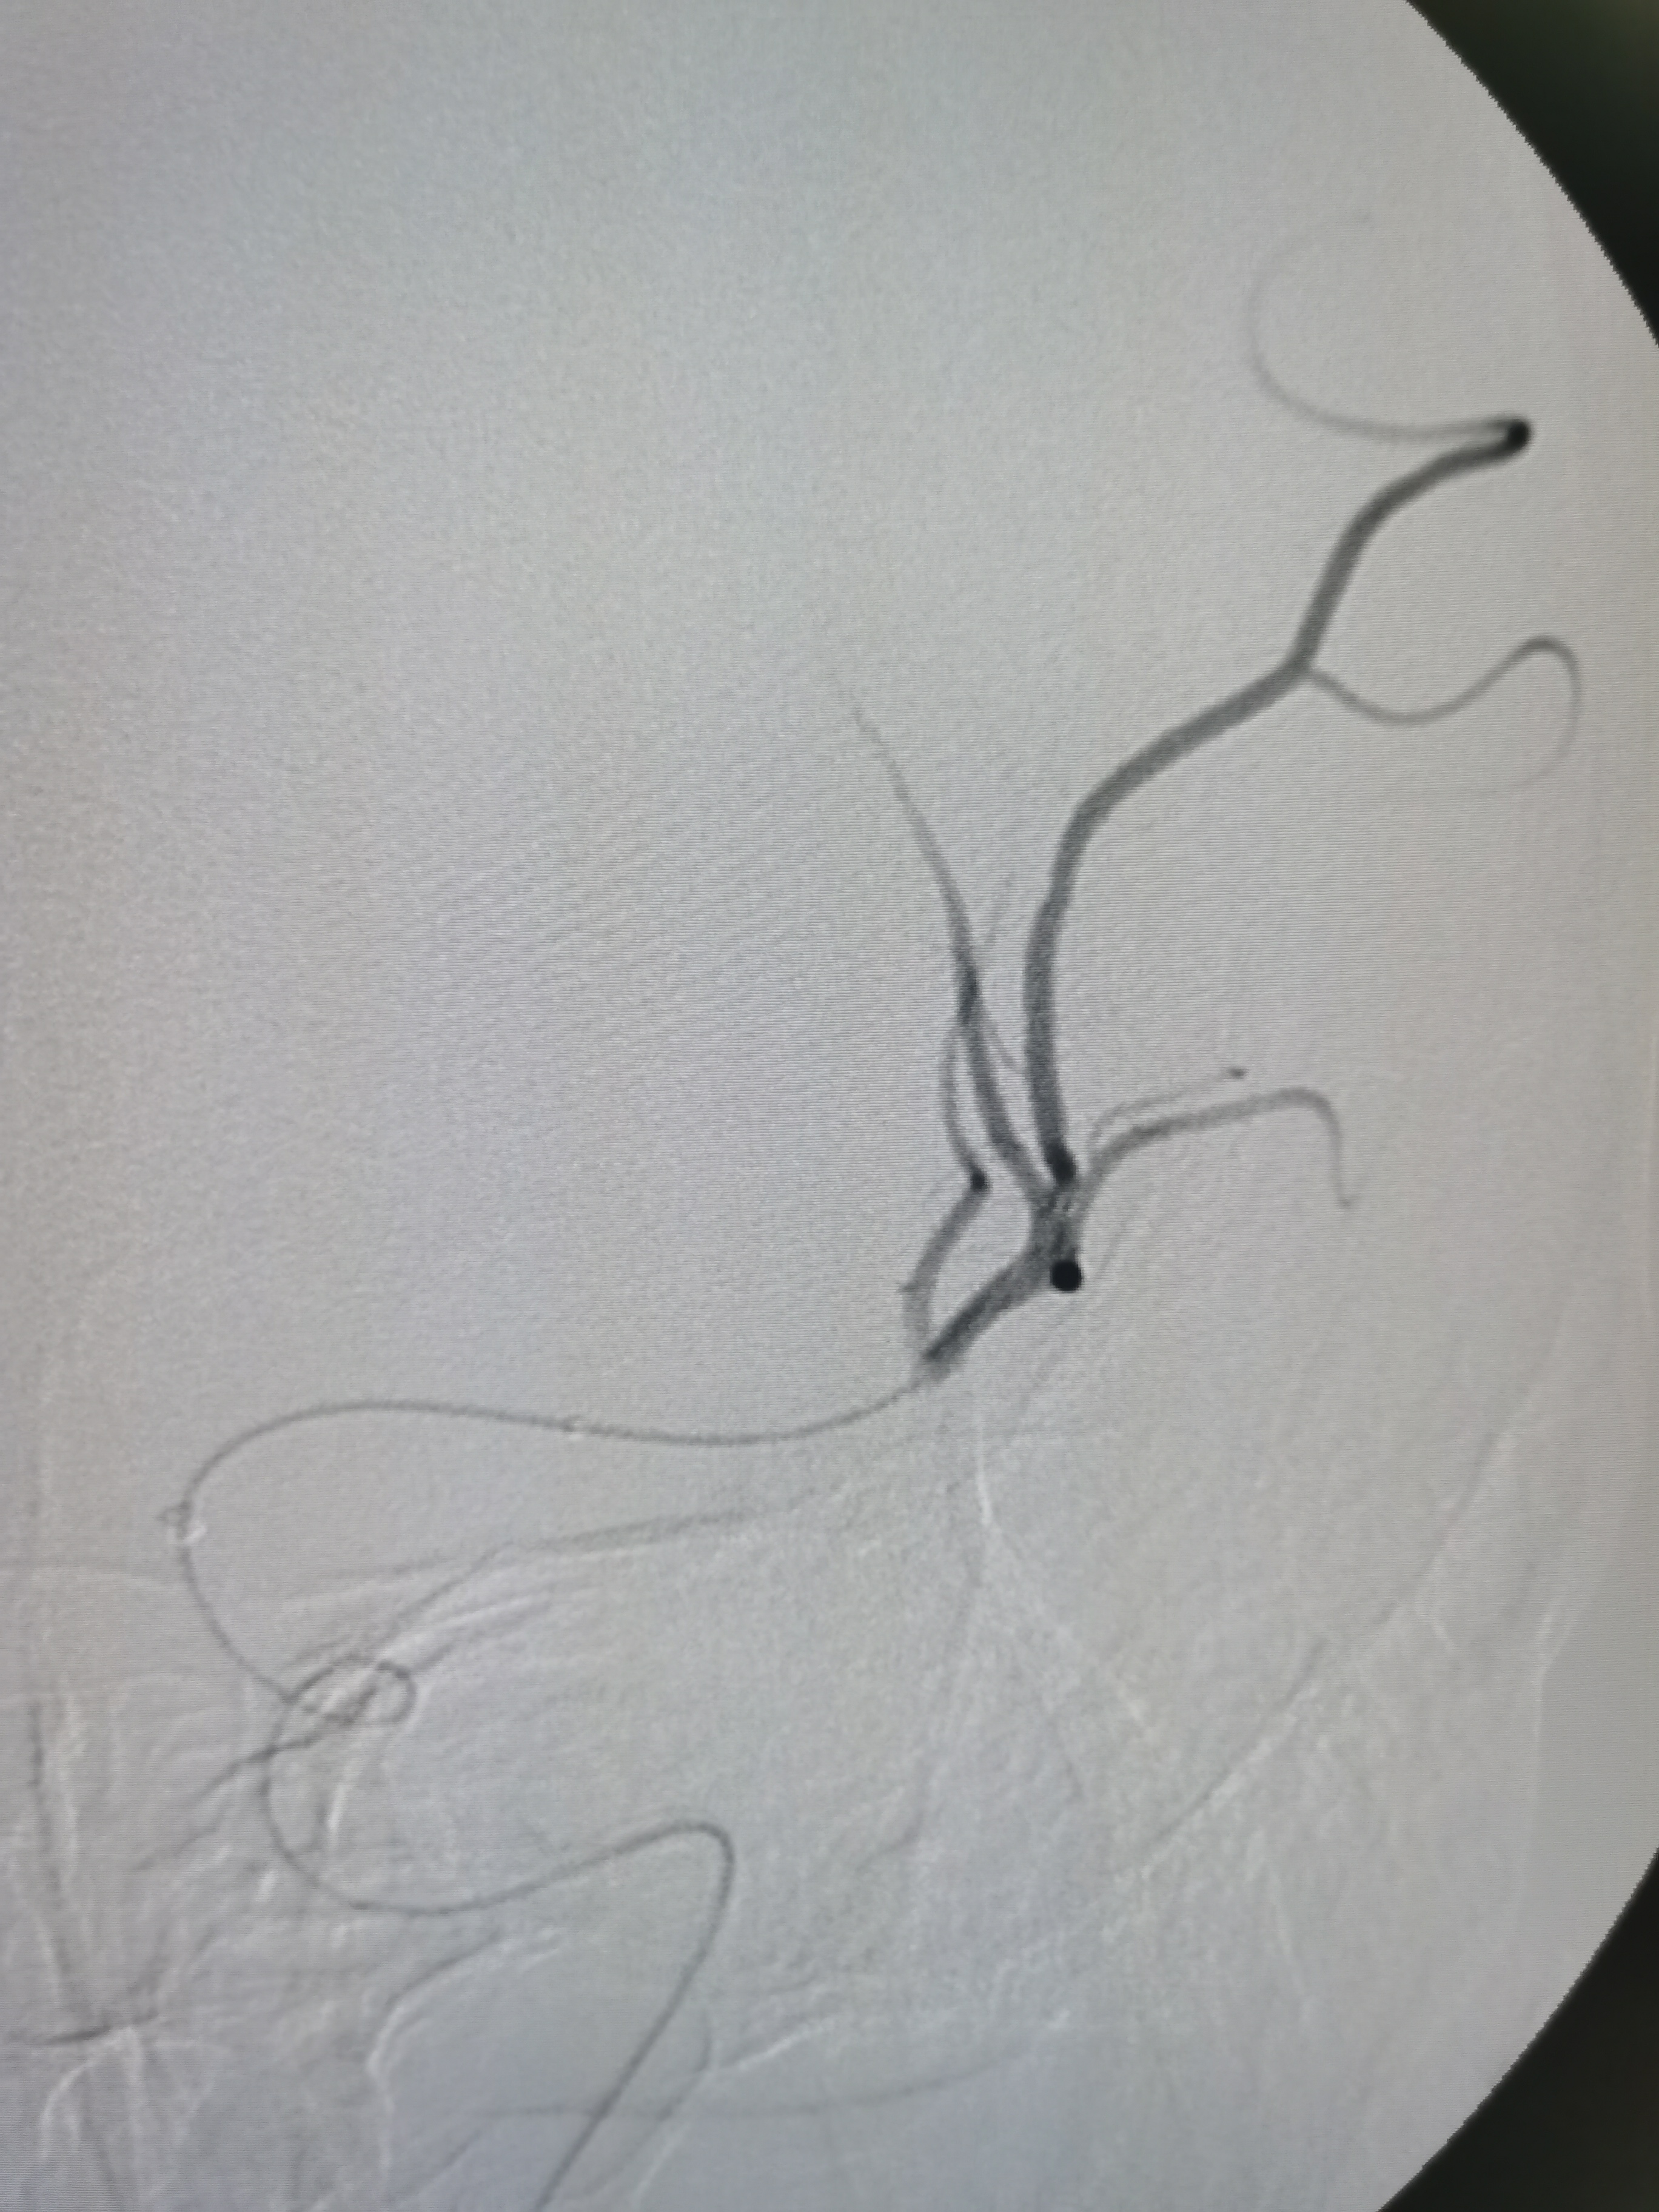

左侧大脑中动脉闭塞,胚胎型大脑后动脉。

动脉晚期可见软膜支代偿远端血供。

8F导引导管及中间导管迅速建立通路,微导丝携微导管顺利通过病变。

微导管确认位于真腔。

4/20取栓支架释放后血管再通。

SWIM技术取栓一次,取出的血栓。